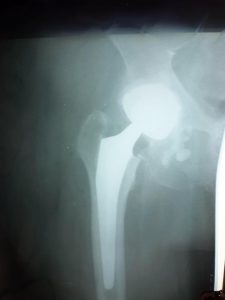

Ендопротезом називають штучно створений засіб або механізм, який може замінити будь-який внутрішній орган людського тіла. Протезування в ортопедії – це метод відновлення анатомічної і функціональної цілісності суглоба, яка була порушеною з приводу будь-якої причини.

“Тлумацька ЦМЛ постійно працює над освоєнням нових методів лікування для надання якісних послуг жителям громади. Нещодавно, вперше на наших теренах, бригадою лікарів з участю професора Сулими В.С. та завідувача травматологічного відділу Мельника В.В. було успішно проведено операцію ендопротезування кульшового суглоба у жінки із переломом шийки стегнової кістки. Пацієнтка почувається добре та швидко йде на поправку”,- йдеться у повідомленні.